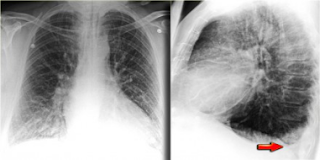

Gambar

1. Edema paru berat karena pemberian cairan intravenous yang

berlebihan.bisa juga terjadi akibat kegagalan jantung atau gimjal,

obat-obatan dan malaria. 2. Penderita yang sama pada hari berikutnya

setelah diberi diuretik dan dilakukan pembatasan cairan. 3. Penderita

yang sama satu minggu kemudian. Adanya perubahan yang cepat dan respon

yang segera terhadap pengobatan merupakan ciri khas edema